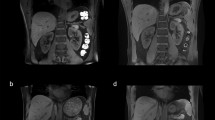

Representative cases are shown in Fig. 5. The MSG-EPI sequences showed homogenous renal artery SI without flow artifacts. However, signal intensity of renal artery is inhomogeneous in b-SSFP because of the presence of flow artifacts. In the qualitative image analysis, all the image quality scores were higher for MSG-EPI than for b-SSFP. The inflow effect appeared as blood signal intensity from none RF excitation area in Fig. 5 (white arrow), because the RF pulse was excited to only the imaging area.

Representative images of a 28-year-old man imaged with MSG-EPI and b-SSFP for three-dimensional renal artery MRA. His heart rate was 66 bpm, and the scan times for MSG-EPI and b-SSFP were 130 and 225 s, respectively. The panels show transverse images for the source and maximum intensity projection for MSG-EPI (a, c, e) and b-SSFP (b, d, f) sequences